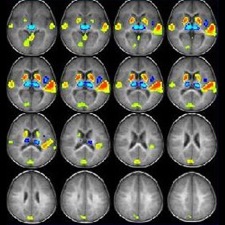

Gracias a la neurociencia y a la tecnología de la resonancia magnética funcional, hoy sabemos que en las personas con Sensibilidad de Procesamiento Sensorial o Alta sensibilidad, el hemisferio derecho registra una mayor actividad; sobre todo en la amígdala y el lóbulo frontal. En este hemisferio es donde está ubicada el área de las emociones, los sentimientos y la creatividad.

En estos estudios se ha comprobado que estas personas tienen una mayor empatía, lo que les facilita colocarse en la realidad de los otros. Se ha observado una mayor cantidad y actividad de sus neuronas espejo (las neuronas especializadas en captar, procesar e interpretar las emociones propias o ajenas). Así, una mayor facilidad para deducir lo que los demás piensan, sienten o hacen, es posible gracias a su activación.